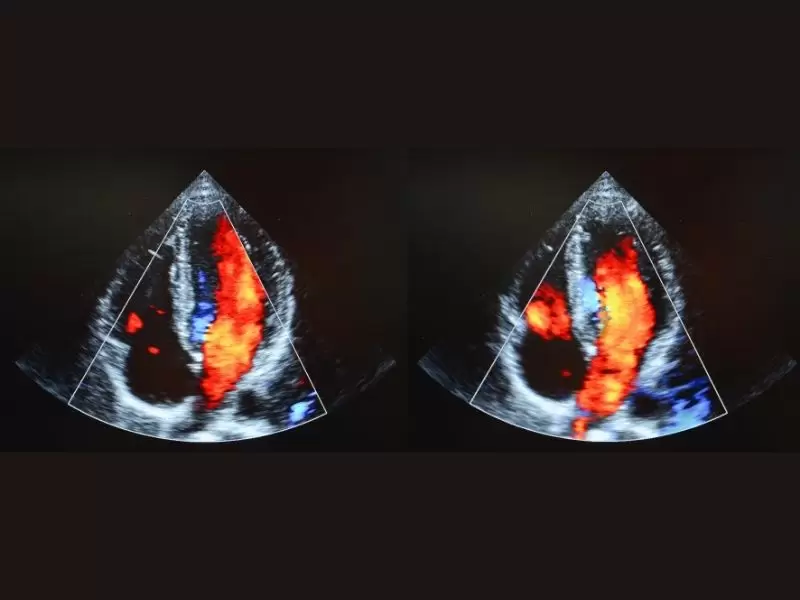

Sağlık Bakanlığı kalite yönetimine göre A Sınıfı (bölgenin en büyük kardiyoloji ve kalp damar cerrahisi) dal hastanesi olarak hizmet vermektedir. 40 standart oda, 2 engelli odası, 8 yatak üçüncü basamak Yoğun Bakım Ünitesi ,laminer floor sistemli 60’ar metrekare büyüklüğünde 3 ameliyathane salonu ve steril depo ,anjio salonu, röntgen, tomografi salonu bulunmaktadır.